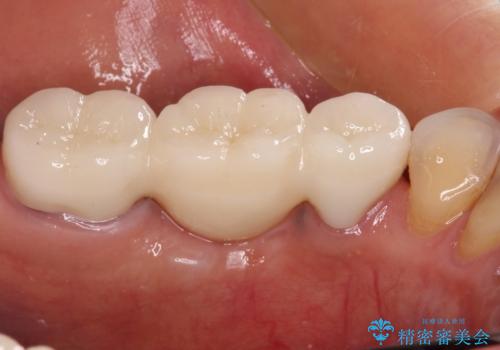

抜歯をしたことで、ずっと気になっていた異臭から解放されました。

前後の歯はいずれも神経が取り除かれている歯であったので、ブリッジ治療では負担が大きくなることが懸念されました。咬合力はさほど強くない咬み合わせであったので、インプラントではなく、ブリッジ治療を選択されました。